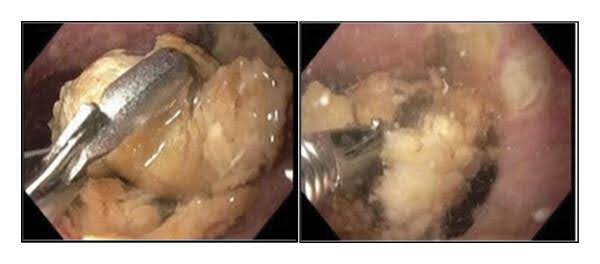

Fig. 3: Gastroscopy1

The 82-year-old patient suffered from an oesophageal bezoar located in the lower oesophagus. It was not possible to remove the bezoar with the help of Raptor forceps and Talon grasping forceps. Bronchoscopy was performed, revealing purulent secretions and food debris in both lungs. Due to the patient's advanced age and comorbidities, surgical intervention was not initially considered. The next treatment attempt was based on direct irrigation of the oesophageal bezoar with carbonated fluids (Coca-Cola) infused with pancreatic enzymes (KREON).